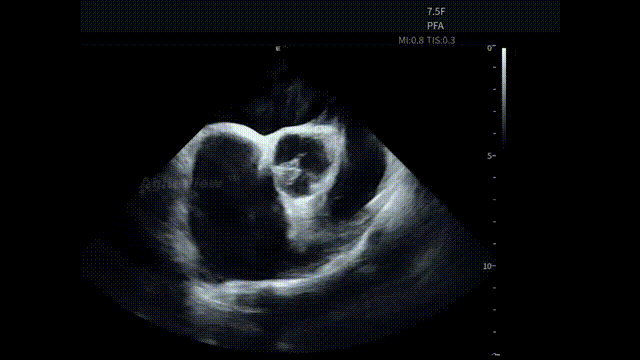

术中,基于AgileView™ ICE 7.5F的产品优势,蒋晨阳主任团队将ICE导管打A弯跨三尖瓣进右室,松弯卡室上嵴,顺转后打到左房长轴切面,以便更好地进行导管封堵/贴靠与位置的判断,在AgileView™ ICE实时影像的指导下,PulseSelect™ 脉冲消融导管安全进入左心房,先后完成双侧肺静脉隔离及MTI、roofline、后壁BOX、SVC隔离, ICE下可见导管贴靠良好,整个消融过程顺利,消融时间约50分钟。术后患者恢复良好。

左房长轴一嵴部贴靠

RSPV